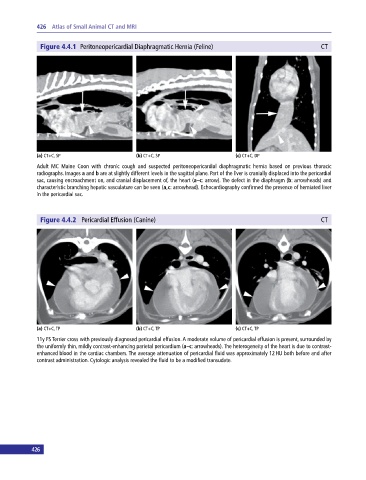

Figure 4.4.1 Peritoneopericardial Diaphragmatic Hernia (Feline) CT

(a) CT+C, SP (b) CT+C, SP (c) CT+C, DP

Adult MC Maine Coon with chronic cough and suspected peritoneopericardial diaphragmatic hernia based on previous thoracic

radiographs. Images a and b are at slightly different levels in the sagittal plane. Part of the liver is cranially displaced into the pericardial

sac, causing encroachment on, and cranial displacement of, the heart (a–c: arrow). The defect in the diaphragm (b: arrowheads) and

characteristic branching hepatic vasculature can be seen (a,c: arrowhead). Echocardiography confirmed the presence of herniated liver

in the pericardial sac.

Figure 4.4.2 Pericardial Effusion (Canine) CT

(a) CT+C, TP (b) CT+C, TP (c) CT+C, TP

11y FS Terrier cross with previously diagnosed pericardial effusion. A moderate volume of pericardial effusion is present, surrounded by

the uniformly thin, mildly contrast‐enhancing parietal pericardium (a–c: arrowheads). The heterogeneity of the heart is due to contrast‐

enhanced blood in the cardiac chambers. The average attenuation of pericardial fluid was approximately 12 HU both before and after

contrast administration. Cytologic analysis revealed the fluid to be a modified transudate.